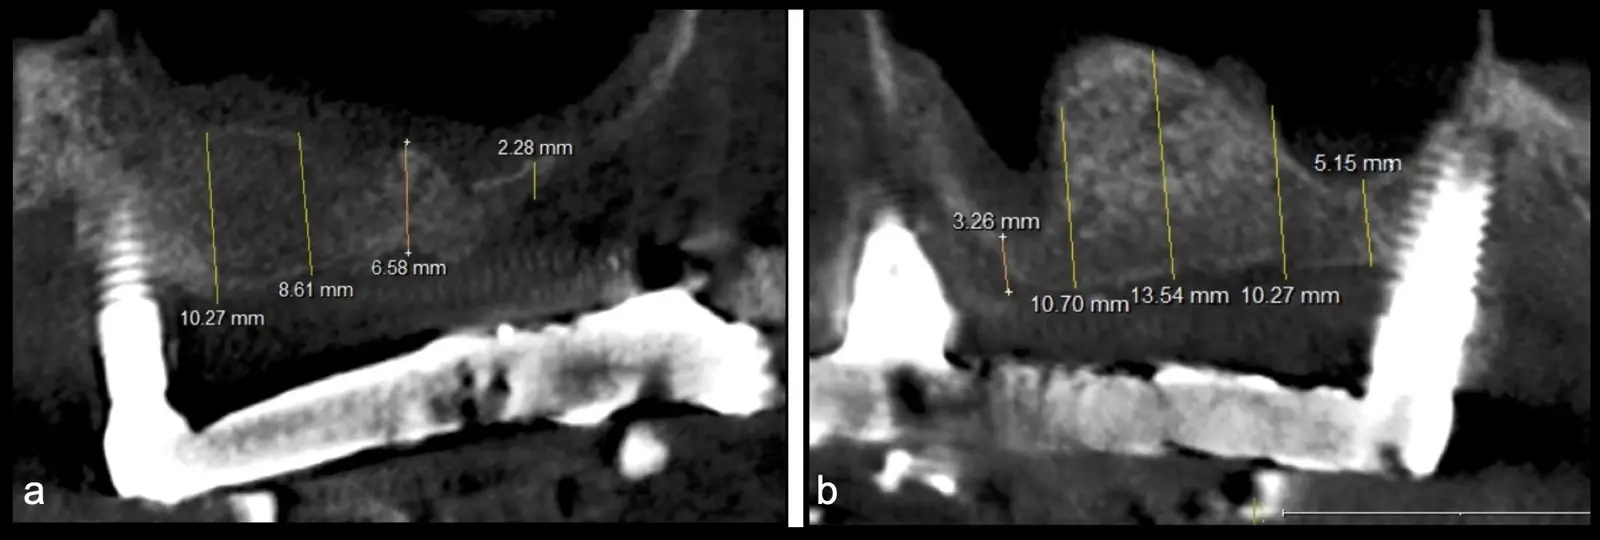

Figura 2. Espesor de la pared lateral (X), altura del reborde residual (Y), profundidad del seno maxilar (Z) y espesor de la membrana sinusal.

Paciente de 62 años, de sexo masculino, llega a la consulta para la colocación de implantes dentales. Refiere haber tenido tratamiento previo con implantes dentales, algunos de los cuales fueron perdidos. A la evaluación clínica se observa ausencia de piezas dentarias en el maxilar superior y 3 implantes remanentes. En la evaluación tomográfica se observa neumatización de los senos maxilares del lado derecho e izquierdo (Figura 14), para lo cual se indica el procedimiento quirúrgico de levantamiento de piso de seno maxilar en ambos cuadrantes, como paso previo a una nueva planificación implantosoportada.

Figura 31. Control tomográfico post operatorio: corte sagital de ambos senos maxilares. (derecha e izquierda).